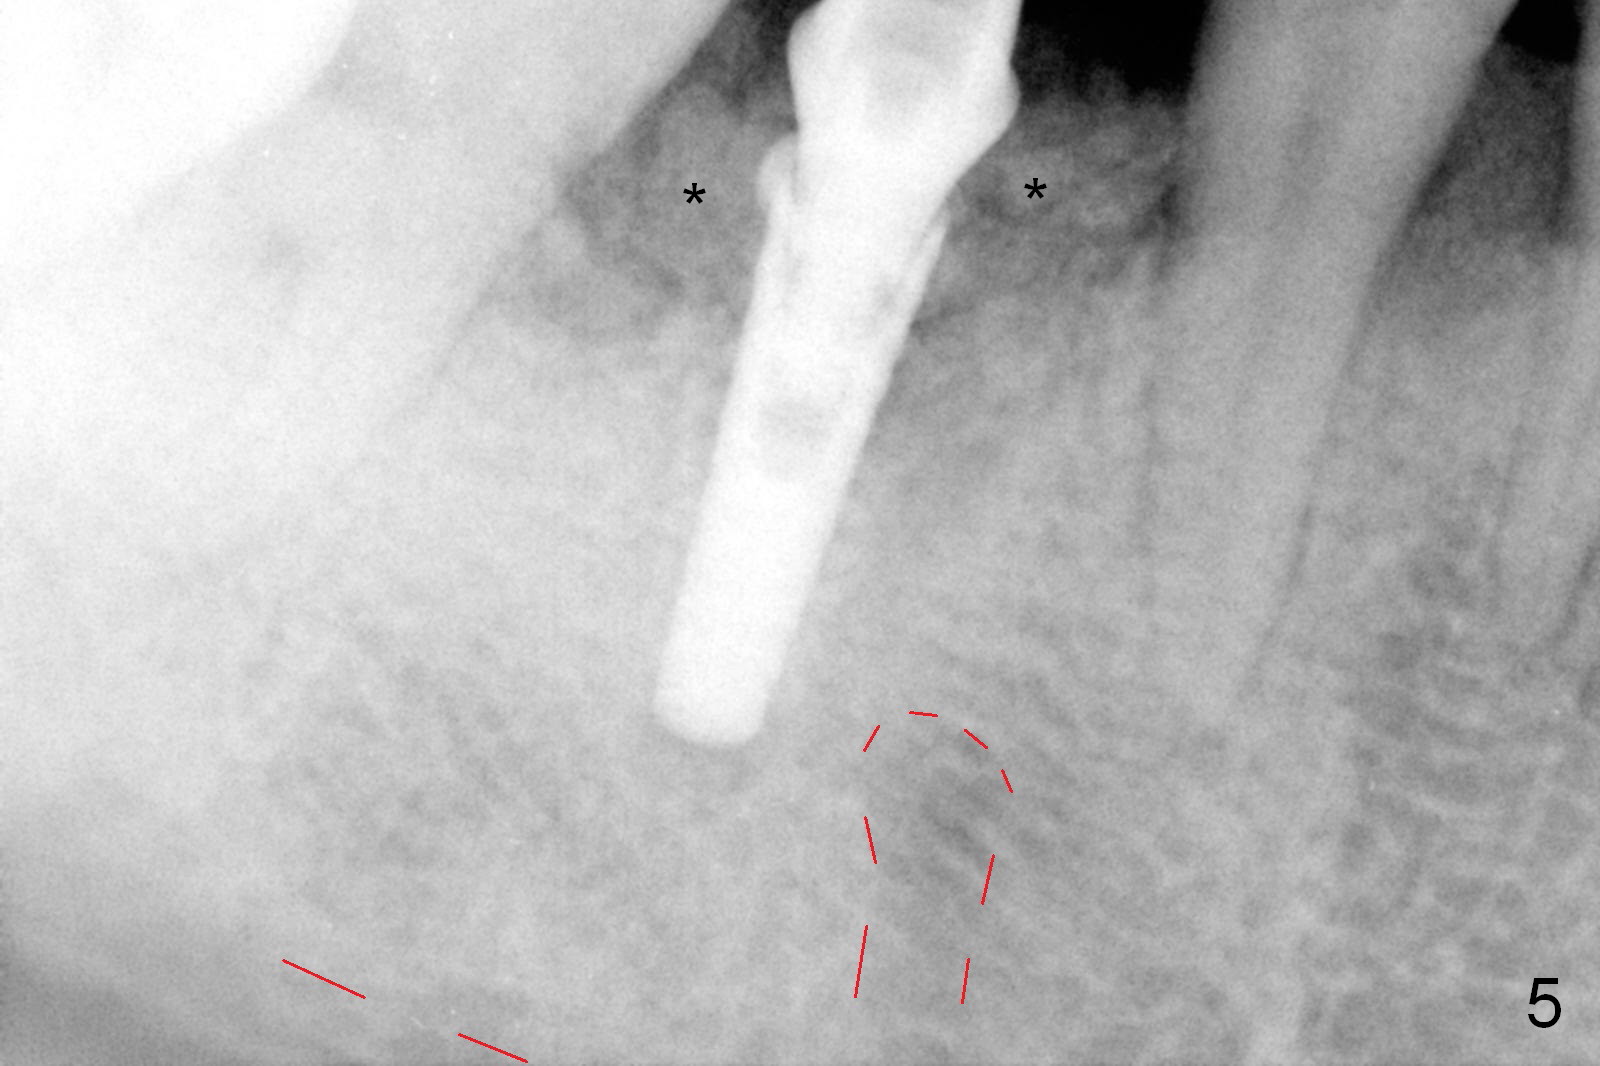

After cleaning the root surface with a surgical curette, a 1.6 mm pilot drill is used to start osteotomy (O) between the mesial (M) and distal (D) roots, followed by a marking bur and 3.8 mm Magic drill 13 mm deep (Fig.1,2). Following root removal, the 3.8 mm drill is reused for 11 mm (Fig.3). After deepening the osteotomy for another 2 mm, a 4.5x13 mm implant is placed with insertion torque of 50 Ncm, followed by allograft (*, .5-2 mm) and a 5x4(2) mm abutment (Fig.4,5). An immediate provisional is fabricated to close the socket (Fig.6 P (lock in)). The detached buccal gingiva (Fig.6 *) is kept in place by applying periodontal dressing (Fig.7 *). Red dashed lines in Fig.1, 3, 5 represents the superior border of the Inferior Alveolar Canal and Mental Foramen.